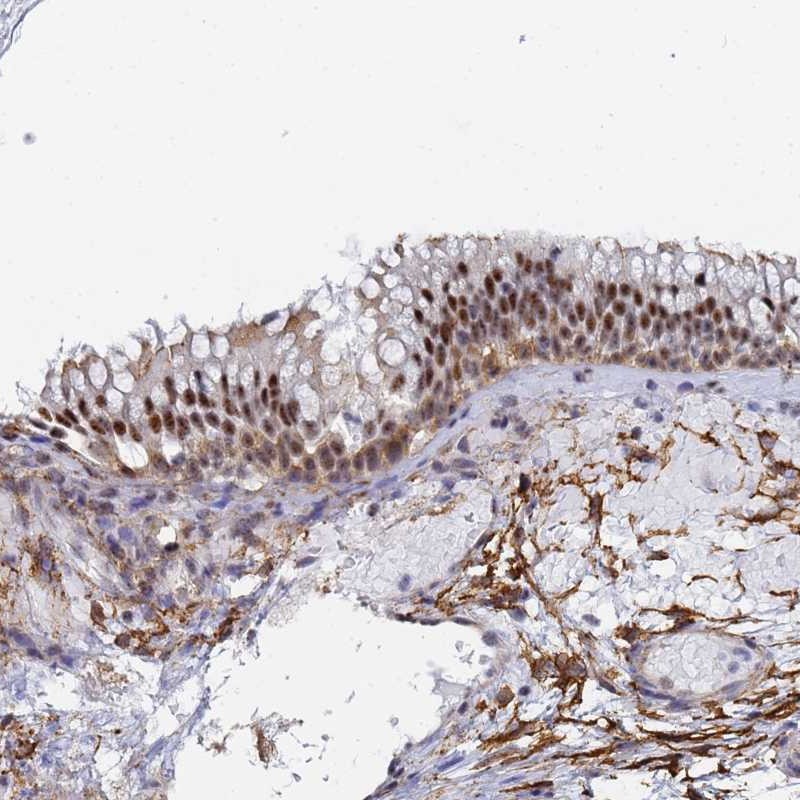

Immunohistochemical staining of human nasopharynx shows strong nuclear positivity in respiratory epithelial cells.